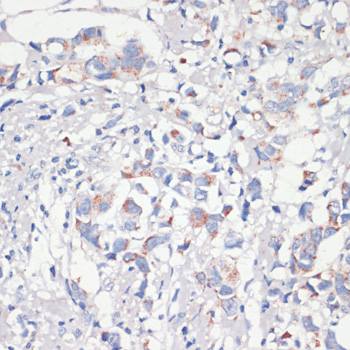

Immunohistochemistry of paraffin-embedded human breast cancer using BCL2 Antibody at dilution of 1:200 (40x lens).